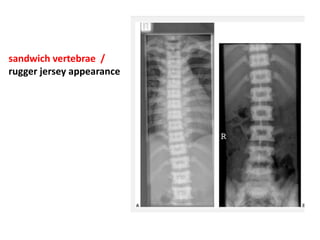

• X-ray findings

• Diffuse osteosclerosis: Bone-within-bone appearance

• Cortical thickening with medullary encroachment

• Erlenmeyer flask deformity = clublike long bones due to

lack of tubulization + flaring of ends

• "Sandwich" vertebrae = alternating sclerotic + radiolucent

transverse metaphyseal lines (phalanges, iliac bones)

indicate fluctuating course of disease

sandwich vertebrae /

rugger jersey appearance